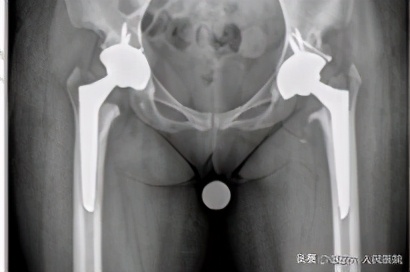

术后

各方都准备完善后,张文生主任团队分两次分别为患者行左、右全髋关节置换,第一次术后第一天患者可以扶拐下地行走,第一次手术后一周又为患者行右侧全髋关节置换术后,第二次又是术后第一天患者扶双拐可以负重下地行走,患者疼痛基本消失。

所幸,随着我国社会的整体进步,医疗材料也有了快速发展,可以说我国材料与国际先进水平相当甚至有超过国际平均水平,北京春立公司生产的130系列髋关节假体正是专门为体型较小的患者设计的一款人工假体,经张文生团队的积极协调,北京春立公司根据患者的身体条件,为患者定制了两套130系列假体。